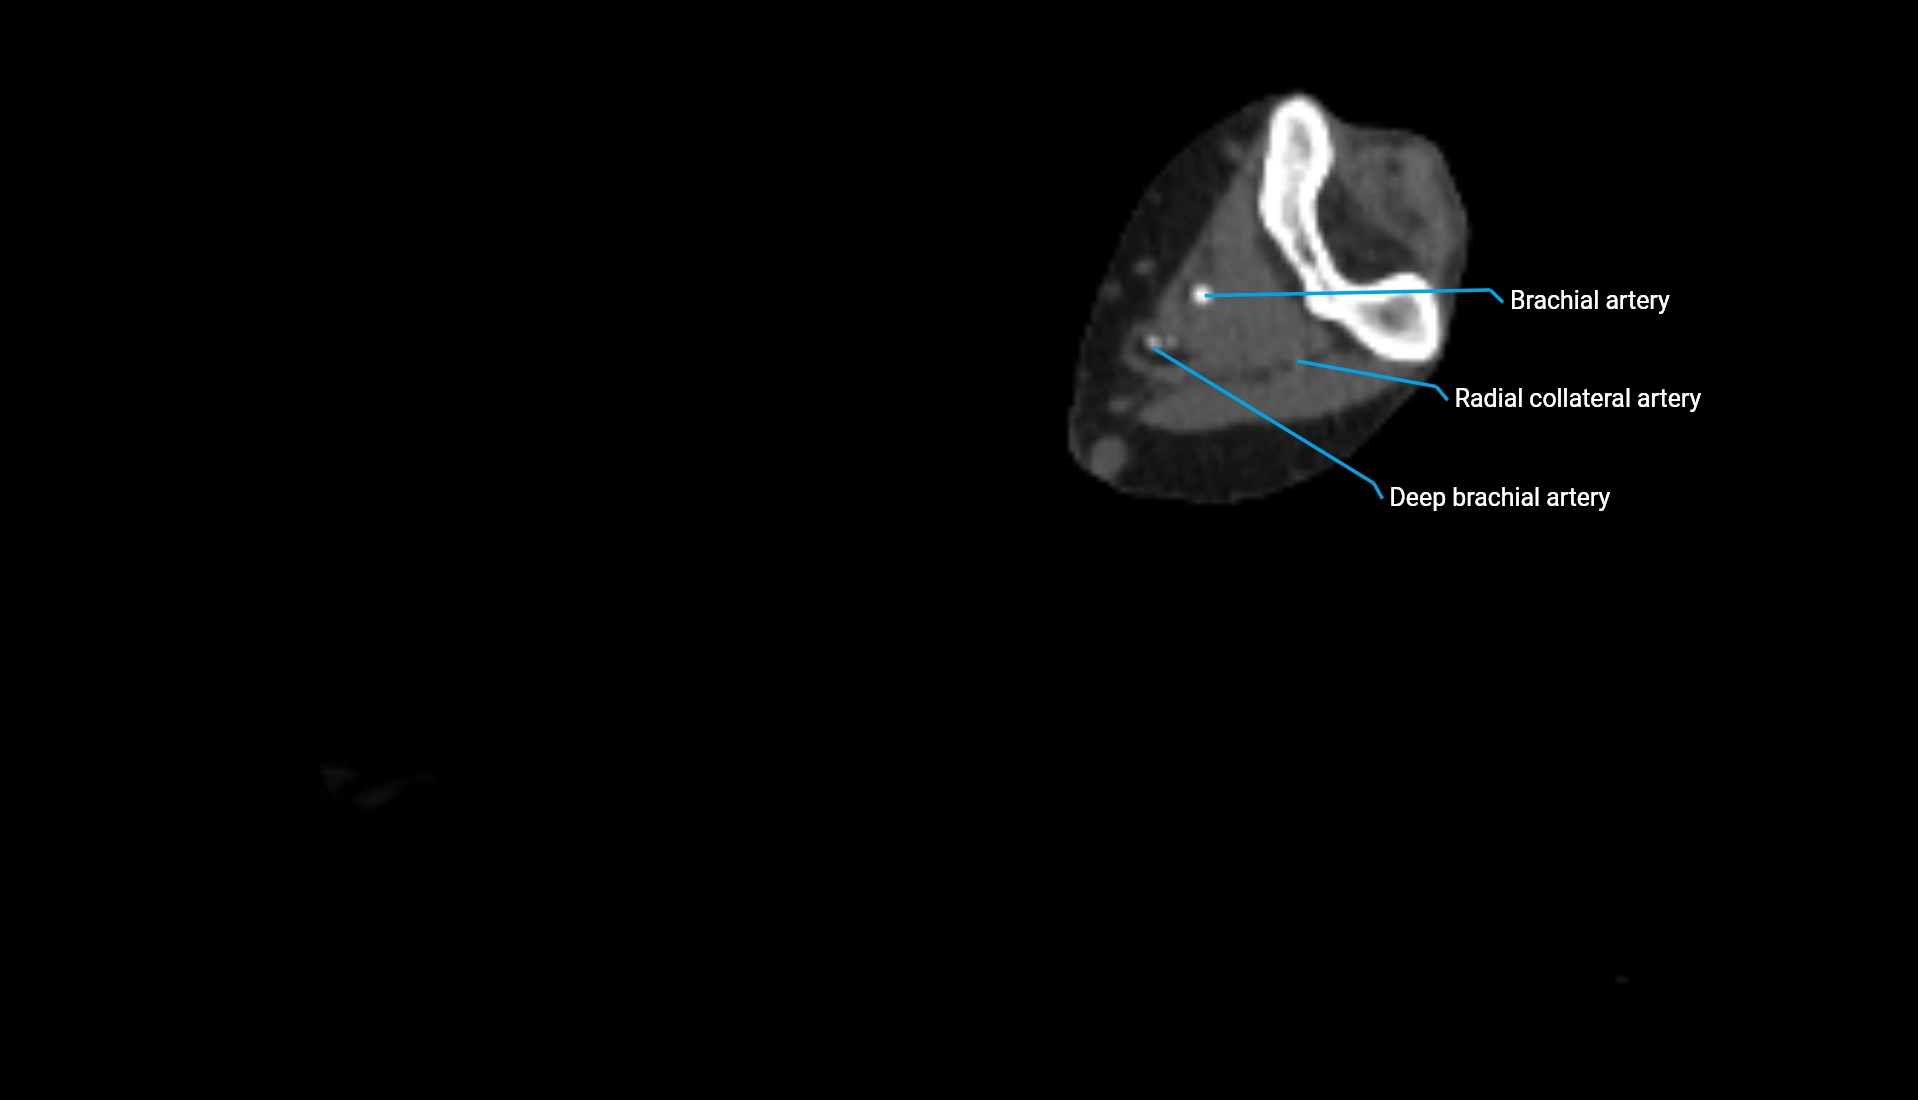

CT Appearance

Non-Contrast CT:

• Cortex: High-density, sharply defined

• Subchondral bone: Dense cancellous matrix

• Articular surface: Smooth concave contour articulating with the capitellum

• Excellent for evaluating bone integrity, alignment, and subtle fractures

Post-Contrast CT:

• Bone: No enhancement

• Joint capsule and synovium: Mild enhancement outlining the joint

• Improves contrast between soft tissues and bony margins

• Useful in detecting subtle joint abnormalities or postoperative changes